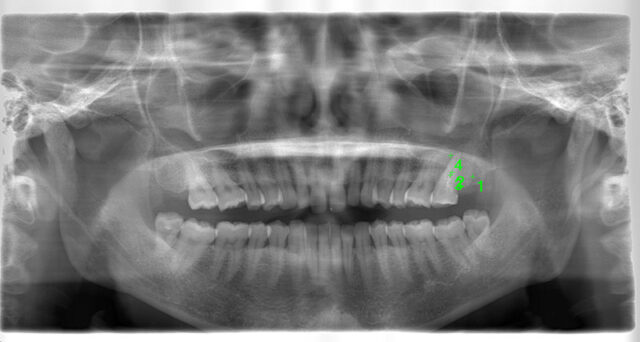

最終補綴物セット後のレントゲン

-